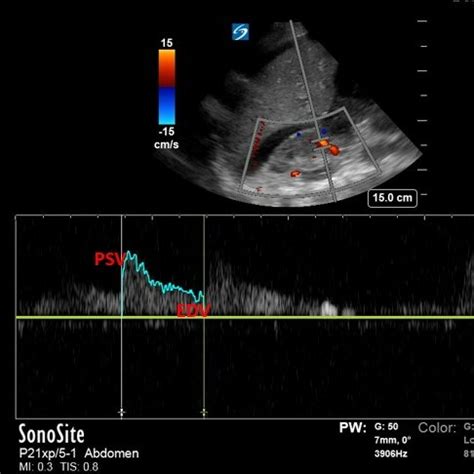

How do doctors diagnose diastolic dysfunction grade 1 ? The primary tool for diagnosing diastolic dysfunction is an echocardiogram. This non-invasive test uses sound waves to create images of your heart. It allows doctors to assess the structure and function of your heart, including its ability to relax and fill with blood.

In grade 1 diastolic dysfunction, the changes in the heart’s filling pattern are often subtle. The cardiologist will pay close attention to certain measurements, such as the E/A ratio. This ratio compares the early (E) and late (A) diastolic filling velocities. In grade 1, the E/A ratio is typically reduced, indicating that the heart is not filling as efficiently during the early phase of diastole.

Another important measurement is the deceleration time of the E wave. This measures how quickly the blood flow slows down as the heart fills. In grade 1 diastolic dysfunction, the deceleration time is often prolonged, indicating that the heart is taking longer to relax and fill with blood.